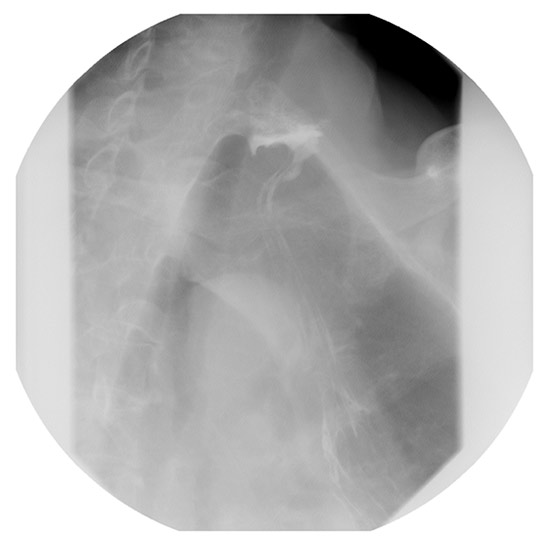

| Figure 4. One year postoperative esophagram showing residual proximal dilatation, but improved transit of contrast through the cervical esophagogastric anastomosis. |

Postoperatively, the patient experienced immediate improvement in the ability to swallow liquids and solids. The patient was discharged on post-operative day two after demonstrating tolerance of a soft mechanical diet. On outpatient follow-up, the patient required an additional bougie dilation. After 1 year, the patient is able to tolerate a solid diet and an esophagram demonstrated improved transit of contrast, with reduced anastomotic narrowing (Figure 4).